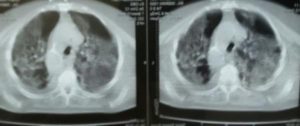

Mjeku i njohur Tritan Kalo ka postuar sot disa grafi te mushkerive te dy te rinjve nen 35 vjec qe ndodhen te shtruar ne spitalin infektiv.

Pamjet jane tronditese dhe qe do te thote se covid prek njesoj te gjitha moshat.

”I prek te gjithe, nuk pyet per moshe, krahune apo ide”, thote Kalo duke porositir serish qe te kohet nje kujdes i madh.

KOHË KOVIDIANE…4.07.2020…Një fundjavë si shumë të tjera në këto muaj sfide me Sars-Cov2/Covid-19….Fillon me “gjimnastikën e mëngjesit”, vajtja në këmbë në QSUT sepse mungojnë urbanët, vijon me mbritjen në pavjon ku të pret Anxhi, një prej infermjereve tona të palodhura e cila gjindet aty pas një natë të ngarkuar, dhe pas veshjes se PPE-ve në pavjon fillojnë vizitat e bisedat për shqetsimet e të smurëve jo të pakët të këtyre javëve te fundit…Një dukuri e veçantë në ecurinë e këtyre ditëve të kësaj “flame mbarëbotërore”, janë shtimet e rasteve në të rinjtë, nën 35 vjeç…Pamje e mëposhtëme alarmuese të CT-Cannereve u përkasin pikërisht dy prej tyre….KURRË mos të harroni se Sars-Cov2/Covid-19 PREK ÇDO MOSHË si dhe lëndon me rrezik jetëmarrëse jo vetëm ata me KOMORBOZITETE dhe MOSHAT e treta.….BËNI kujdes vëllezër e motra….Zbatoni me bindje e përpikmëri këshillat e PROFESIONISTËVE për distancim fizik, higjenë personale, ajrim të mjediseve, ushqim, rehidrim, mbajtjen e maskave në mjediset e mbyllura apo të mbipopulluara….Përkujdesuni si për jetët tuaja por edhe të atyre që gjallojnë pranë jush…Tirana këto kohët e fundit sikur “nuk e ndjen fare” erën e dezinfektimit të rrugëve dhe të mjediseve publike, e jo vetëm…HIGJENA kolektive është një domozdoshmëri në këtë sfidë…..Po ashtu miq, kolegë, dashamirës dhe bashkëkombas, Sars-Cov-2/COVID-19 NUKU ka përkatësi partiake dhe ajo nuk “përkëdhel” të majtët apo të djathtët…Është nje virus sëmundje-shkaktues dhe jetë-marrës “Pa dallim Feje, Krahine dhe Ideje”…..MIRËBESIMI reciprok dhe NDËRGJEGJËSIMI kurrë nuk duhet t’ju mungojë….ASGJË nuku është e pamundëshme kur NE bëhemi bashkë në përpjekjet tona….Gjelbërimi e frutëzimi i ullinjve në oborrin e spitalit Covid-1, Shërbimi i Sëmundjeve Infektive në QSUT, janë një dëshmitar i këtij optimizmi real….Together forever!!!